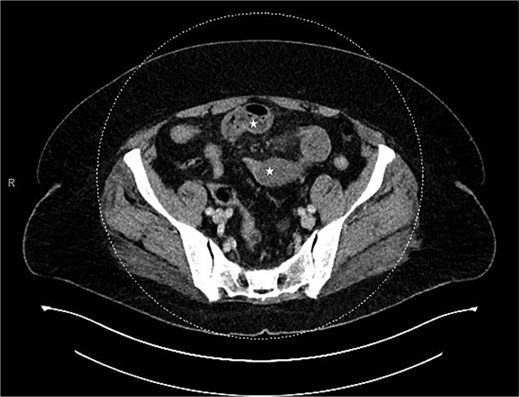

Due to imaging findings and ongoing clinical concern for impending bowel compromise, the patient was taken to the operating room urgently and underwent a diagnostic laparoscopy. Intraoperatively, the appendix was found to be inflamed at the tip and it was adherent to the lateral abdominal wall (Fig. 3). The appendix was forming a band encircling a loop of small bowel, resulting in a mechanical obstruction (Fig. 4). Lysis of the adhesions was performed, successfully freeing both the appendix and the entrapped segment of small bowel (Fig. 5). The involved bowel segment appeared hemorrhagic but was not frankly ischemic, therefore bowel resection was not needed. A laparoscopic appendectomy was subsequently performed. The excised appendix measured 7 cm in length (Fig. 6). The obstruction was resolved, and the patient tolerated the procedure well. She had an uncomplicated postoperative recovery. She started passing gas and tolerated oral intake on postoperative day 1. She was discharged on postoperative day 2. At her follow-up clinic visit, her incisions were well-healed. She reported normal bowel function, no abdominal pain, and was gradually resuming her regular activities. Overall, she was recovering well, with no concerns.

The appendix forming a band around the small bowel, causing small bowel obstruction (star).